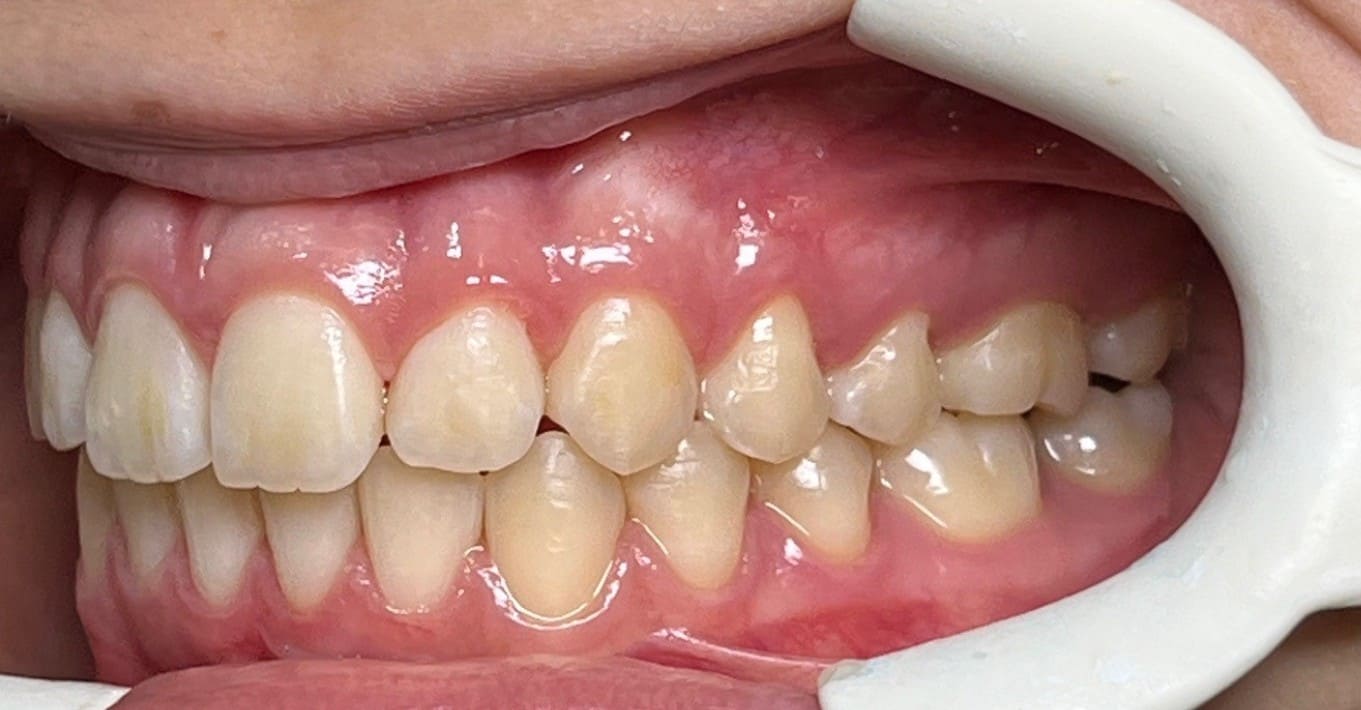

Initial

Final